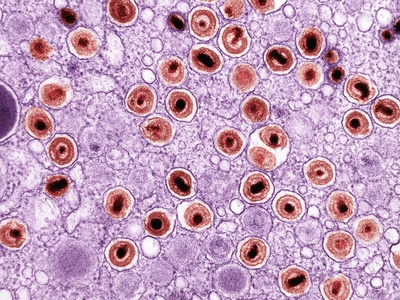

Cytomegalovirus infection (CMV)

CMV commonly causes mild or asymptomatic infections but can cause severe disease in newborns and immunocompromised people, including organ transplant recipients. Transmission is via body fluids and perinatal routes. No general vaccine yet; prevention focuses on hygiene and donor screening.